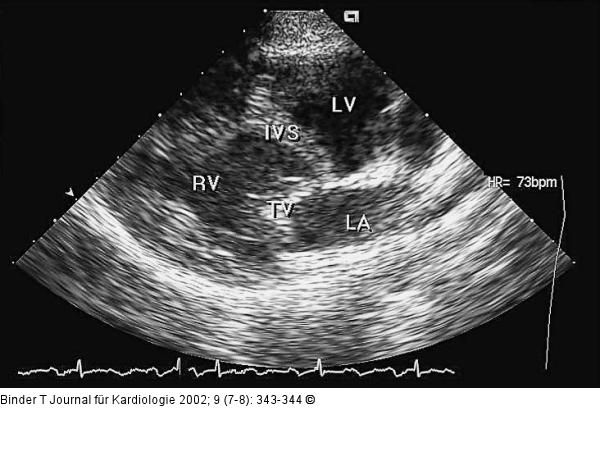

Abbildung 1: Kongenital korrigierte Transposition der großen Gefäße (ccTGA) Parasternale lange Achse. Anstelle des linken Ventrikels (LV) findet sich ein morphologisch rechter Ventrikel (RV). Da die AV-Klappe immer mit dem jeweiligen Ventrikel assoziiert ist, sieht man in der parasternalen langen Achse die Trikuspidalklappe (TV); IVS = interventrikuläres Septum. |

Parasternale lange Achse. Anstelle des linken Ventrikels (LV) findet sich ein morphologisch rechter Ventrikel (RV). Da die AV-Klappe immer mit dem jeweiligen Ventrikel assoziiert ist, sieht man in der parasternalen langen Achse die Trikuspidalklappe (TV); IVS = interventrikuläres Septum. |